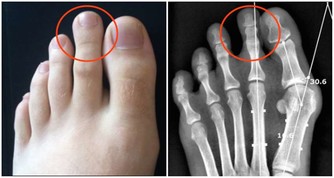

拇指疼痛:拇指中少商經穴與肺息息相關。如肺有疾病,壓這個部位是會會痛得

跳起來。